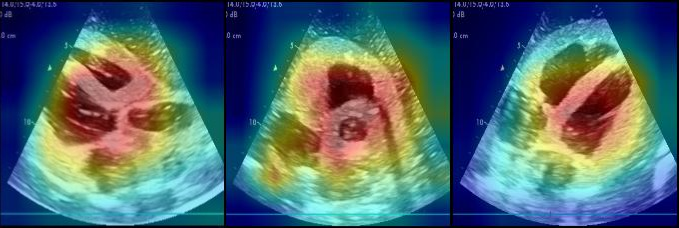

An additional key aspect to consider is the interpretability of the proposed AI framework. Explainable artificial intelligence (XAI) is an emerging field focused on making DL models interpretable, enabling users to understand the reasons behind specific predictions by highlighting the relevant features in the input image that contributed to the model’s output [45]. In the medical field, comprehending the behavior of DL models is essential, as it directly influences clinical decisions and outcomes. In this context, our work focuses on gaining insights into how the proposed AI framework performs both classification and grading tasks, offering a specific case for understanding model behavior in medical applications. To achieve this, we have selected Gradient-weighted Class Activation Mapping (Grad-CAM), one of the most widely used methods for explainable DL, with its variant Grad-CAM++ [46, 47]. The results are presented in Figures 15 and 16. In the Grad-CAM++ heatmap, different colors represent the intensity of focus by the model. Red indicates the areas the model considers most important, while yellow and blue represent decreasing levels of attention. From these visualizations, we observe that the AI framework predominantly focuses on the central region of the image (highlighted in red), which corresponds to the identification of the four chambers in the PL US cardiac image. Similarly, in the PSAV and SC cardiac views, the model focuses on the areas where the structure of the view is clearly delineated. This suggests that the model prioritizes this cardiac structural features for both classification and grading tasks.

Refer to caption

Fig. 15: Grad-CAM++ visualizations for the classification model: PL (left), PSAV (middle), and SC (right)

Fig. 16: Grad-CAM++ visualizations for the grading model: PL (left), PSAV (middle), and SC (right)